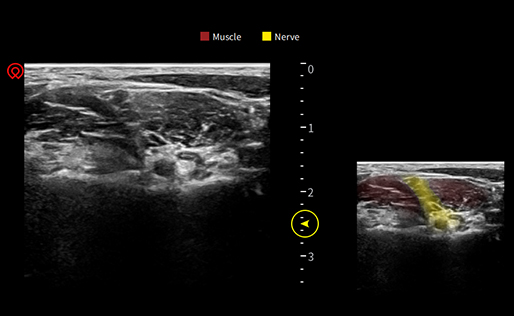

wiNerve

Reconnaissance intelligente des nerfs par IA

Reconnaissance en temps réel

Soutenir plusieurs nerfs

Excellentes images cliniques